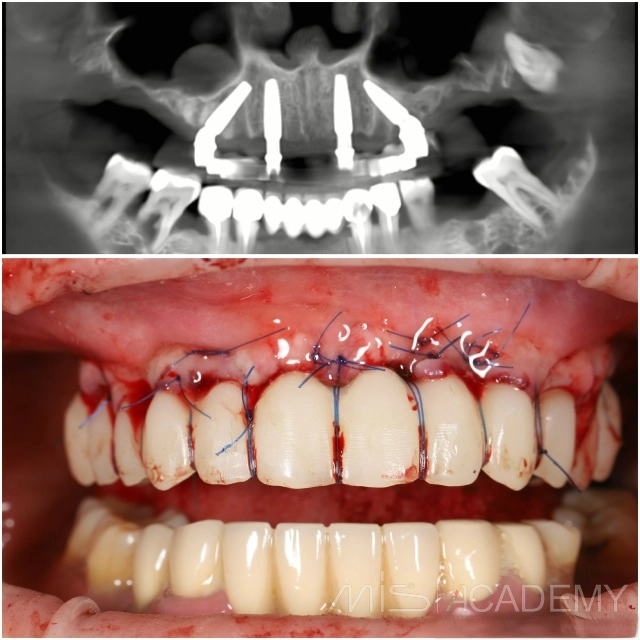

💢 Василий Бочаров г. Владивосток. Продолжение кейса: https://t.me/misrussia/6399 Установили по 4 имплантата на верхней и нижней челюсти и провели немедленную нагрузку металлопластмассовыми конструкциями....